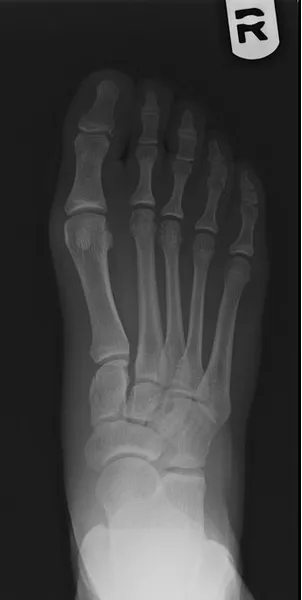

Below is the case of a young female athlete was injured while playing soccer, she had pain and swelling at the midfoot. MRI imaging confirmed ligament rupture. The procedure was done percutaneously with flourscopic guidance. Pictured on the left is pre operative and post operative x-ray to the right. She went on to heal uneventfully after physical therapy, and has since returned to playing soccer.

This is an example of an injury to the arch of the foot involving the Lis Franc's ligament between the base of the 2nd metatarsal and the medial cuneiform bone. This is a very important stabilizing ligament of the foot (left). This injury is repaired surgically with screws, pins and occasionally surgical plates. This case was corrected with a combination of screw and pins (right).

The images below demonstrate Lis Franc's ligament rupture with increased spacing between the medial cuneiform and the intermediate cuneiform. The ligament is attached between the base of the 2nd metatarsal and the lateral aspect of the medial cuneiform (left). The post-surgical repair with screw fixation (right) shows reduction in that aforementioned space between the cuneiforms re-establishing the stability of the medial midfoot.